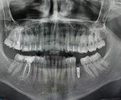

علاج الزرعات